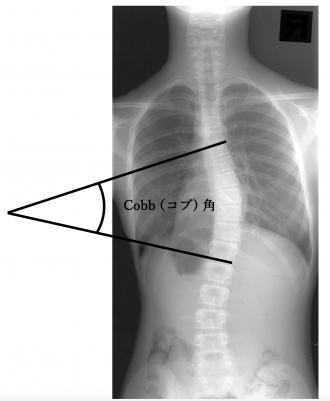

側弯症は、レントゲン検査によって診断され、背骨の弯曲の程度は図のように、「コブ角」という指標で表されます。「コブ角」とは、脊柱の上下で最も曲がりの強い椎体から直線を伸ばし、その2本の直線の交差する角度のことを示します。

この「コブ角」が10°以上の場合、「側弯症」と診断されます。